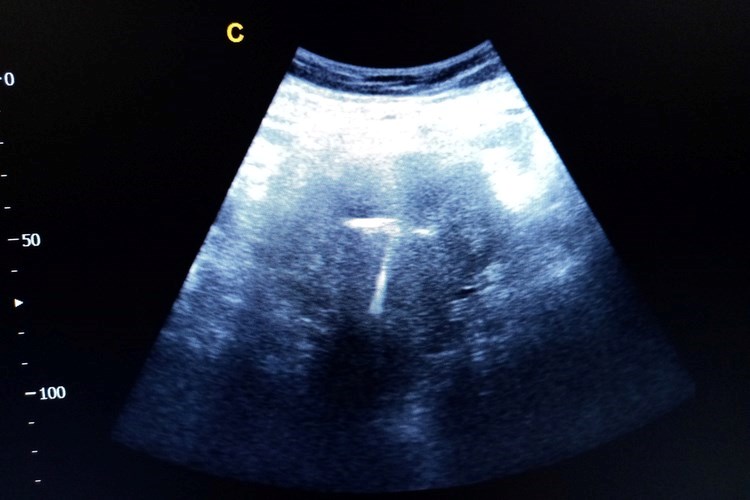

עבור נשים שלא ילדו ולא מעוניינות בגלולות, מדובר בבשורה של ממש. ההתקן התוך רחמי הוא אביזר המוחדר לרחם על ידי רופא, נשאר שם למשך שלוש עד חמש שנים (ניתן להוציאו בכל עת), ובזמן הזה הוא מונע הריון בצורה יעילה ביותר ואפילו ברמה גבוהה יותר מזו של הגלולות. היתרונות משמעותיים: אין צורך לזכור ליטול גלולה כל יום, תופעות הלוואי של ההתקן ביחס לגלולות הן נמוכות ולעתים כלל לא קיימות, והוא נוח ובטוח לשימוש.

ההתקנים מתחלקים לשני סוגים עיקריים: התקני נחושת שאינם מכילים כלל הורמונים והתקנים הורמונליים. ד"ר הר טוב מסביר שתופעת הלוואי העיקרית של ההתקן הלא הורמונלי היא עלייה בכמות הדימום בזמן הווסת, לעתים במידה מועטה אבל לעתים במידה כזו שגורמת לאנמיה עד כדי צורך להוציא את ההתקן. יש התקני נחושת קטנים, כך שהם מתאימים גם לנשים שלא הרו בעבר ולא מעוניינות כלל בהכנסת הורמונים לגופן.

ההתקנים ההורמונליים קיימים בשלושה מינונים: "מירנה", שהוא בעל המינון הגבוה ביותר והוא גם גדול יותר ולכן לרוב אינו מומלץ לנשים שלא הרו בעבר. ישנם שני התקנים קטנים יותר שמתאימים גם לנשים שלא הרו וילדו: התקן "קיילינה", שפעיל למשך חמש שנים, והתקן "ג'נס", בעל מינון הורמונלי נמוך יותר, שפעיל למשך שלוש שנים. שני ההתקנים האלה צברו יותר ויותר פופולריות בשנים האחרונות בקרב נשים שלא ילדו.